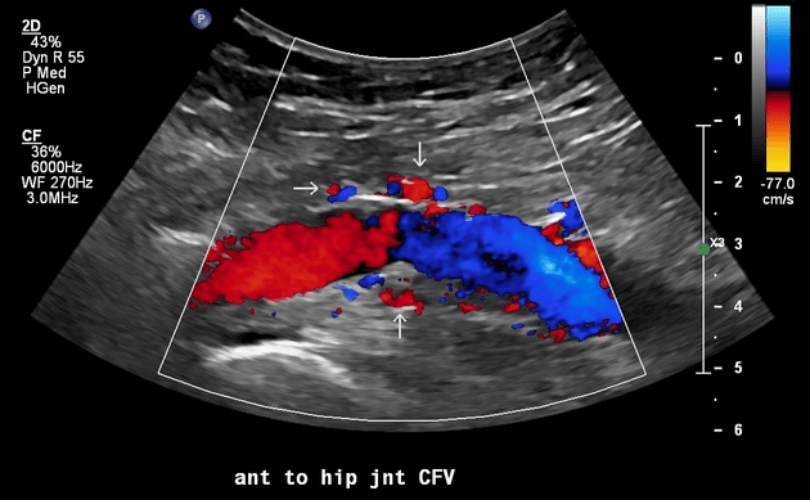

Duplex Ultrasonogram of Peripheral artery & Vein, AVM, LVM, A-V fistula study